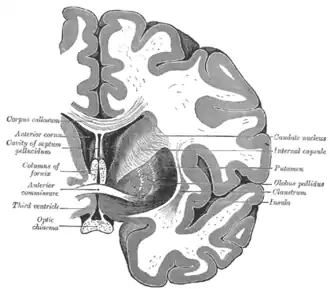

The caudate nuclei are near the center of the brain, sitting astride the thalamus. There is a caudate nucleus in each hemisphere of the brain. Each nucleus is C-shaped, with a wider "head" (caput in Latin) at the front, tapering to a "body" (corpus) and a "tail" (cauda). Sometimes a part of the caudate nucleus is called the "knee" (genu).[6] The caudate head receives its blood supply from the lenticulostriate artery; the tail of the caudate receives its blood supply from the anterior choroidal artery.[7]

The head and body of the caudate nucleus form part of the floor of the anterior horn of the lateral ventricle. The body travels briefly towards the back of the head; the tail then curves back toward the anterior, forming the roof of the inferior horn of the lateral ventricle. This means that a coronal section (on a plane parallel to the face) that cuts through the tail will also cross the body and head of the caudate nucleus.